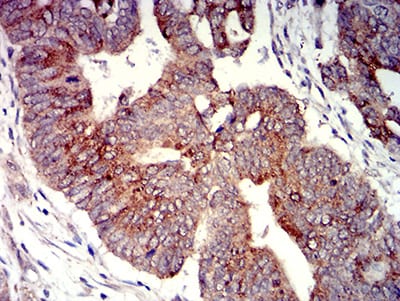

分类: 科研抗体货号: 31308别名: P2Y8应用: IHC,IF,FCM反应种属: Human